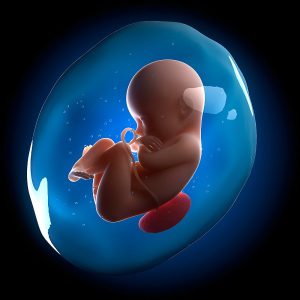

Nước ối giữ vai trò quan trọng đối với quá trình phát triển của thai ...

Nước ối không chỉ đóng vai trò quan trọng với thai nhi ngay từ khi ...